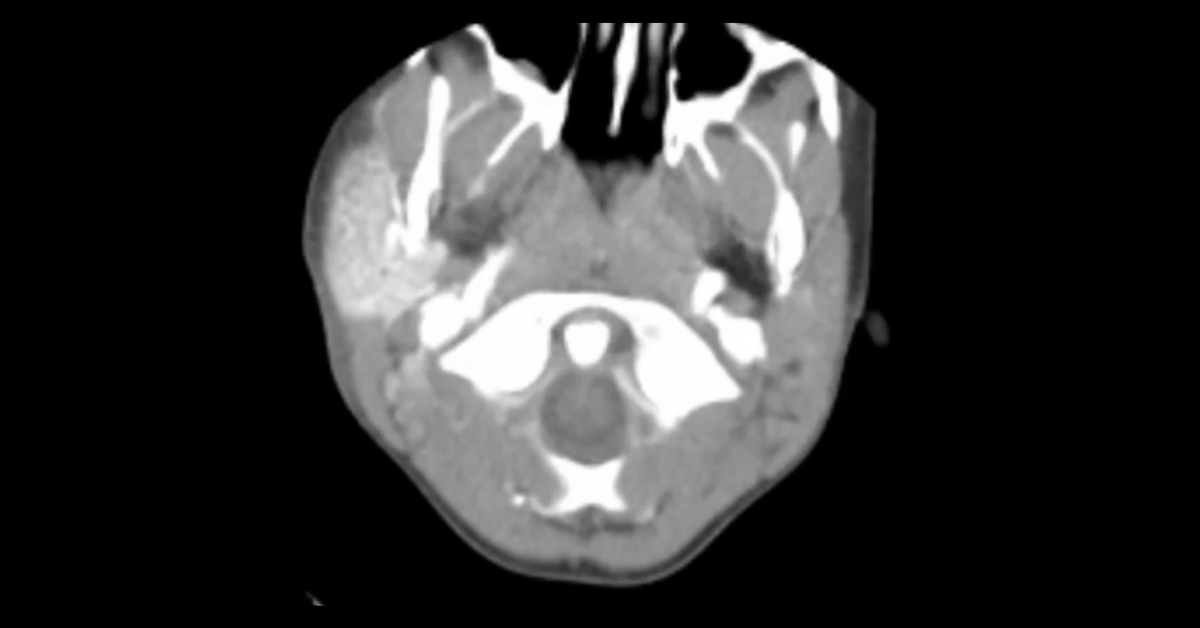

Cases of pediatric head and neck pathology, including abusive trauma and congenital abnormalities.

1. Learn the key differentiating points in diagnosing a “fluid-filled” cranial vault.

2. Learn the multiple potential locations of subdural hemorrhage in abusive trauma.

3. Understand the locations and appearance of cerebral infarcts from abusive strangling.